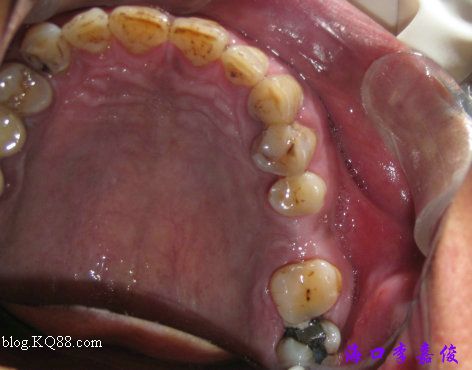

下牙術(shù)前